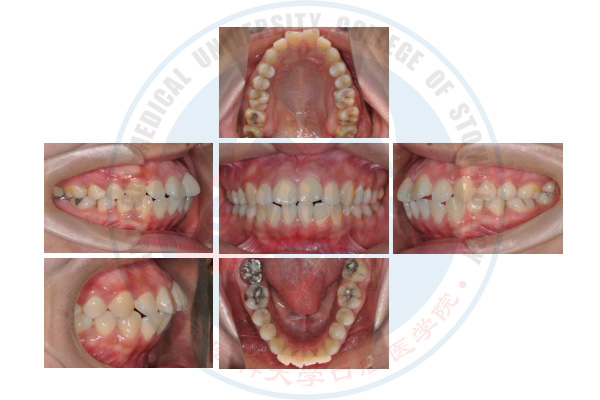

正畸治疗前

正畸治疗后